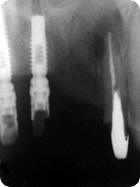

Retratamento Endodôntico

Retratamento Endodôntico 1

Retratamento Endodôntico 2

Retratamento Endodôntico 3

Retratamento Endodôntico 4